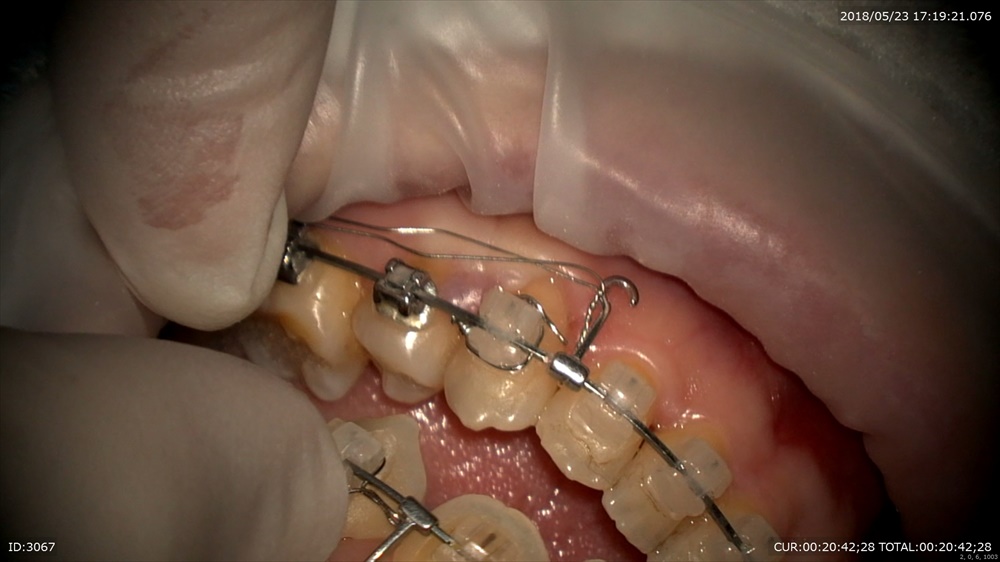

そこでこのようなワイヤーをIN。トルクもIN

パッジブタイバックも忘れずに。スペースが開いてしまわないように。